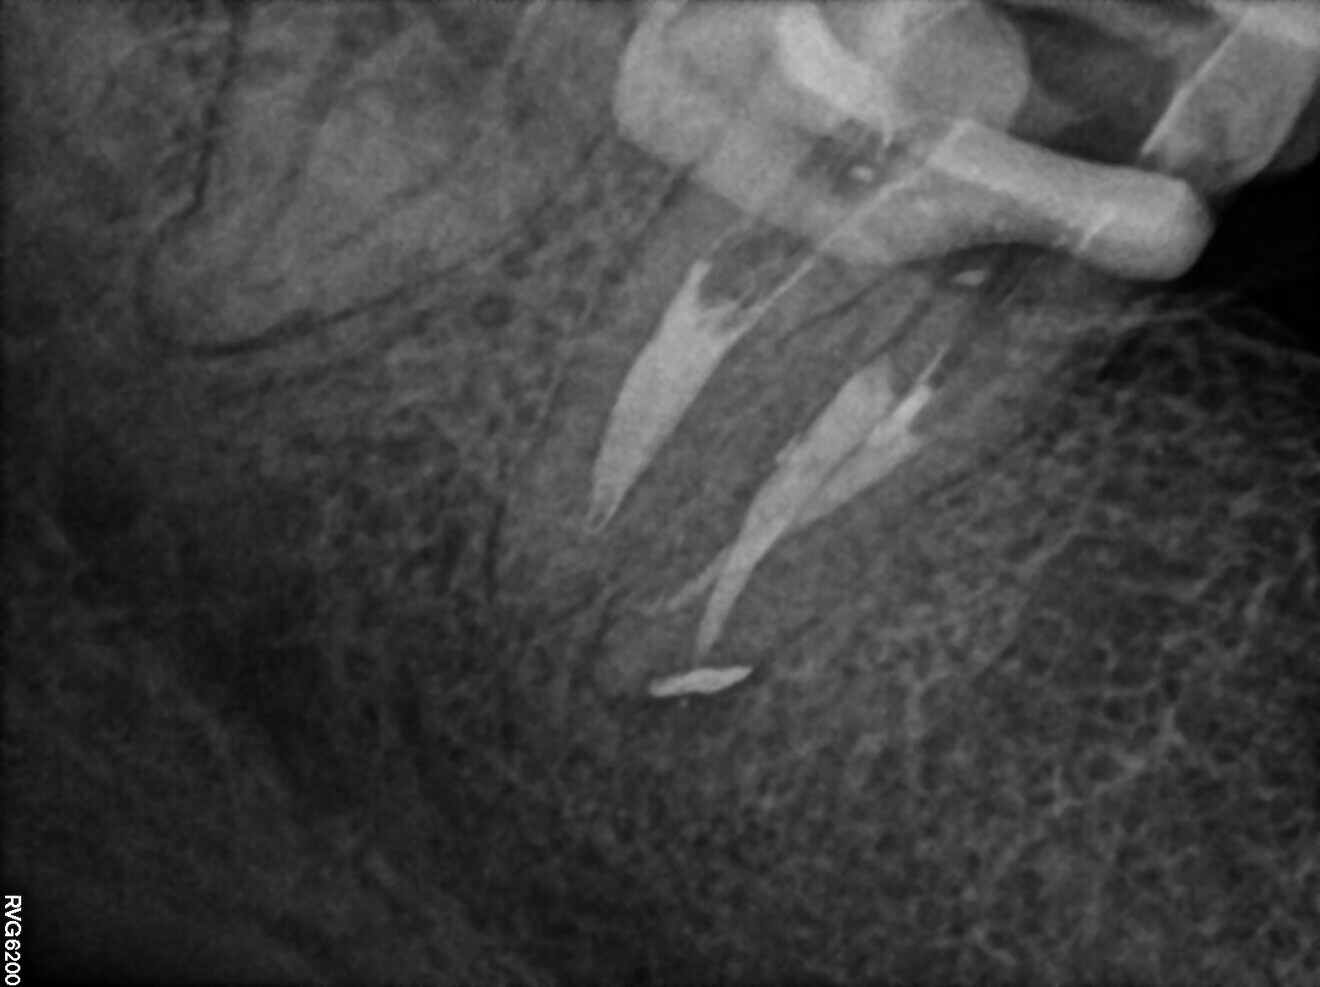

During the second appointment, sodium hypochlorite 5,25% was activated with SkyPulse in AutoSWEEPS mode for most of the treatment. It was very important that the laser tip that was placed below the root canal orifice but without touching the root canal walls. This is a very important modification of the techniques introduced by Giovanni Olivi. The standard technique of AutoSWEEPS activation requires activation of the irrigants with the laser tip above the orifice pointing in a different directions during the activation cycle. In the case of non-patent canals, placing the fibre below the orifice works in a much more effective way. After every five to six cycles of sodium hypochlorite, 17% EDTA was used. After every sequence of AutoSWEEPS activation, the canals became more patent in the deeper segments. C-PILOT files were used to enlarge the canal space. After reaching an additional 2–3 mm of the working length, the rotary file was used to enlarge the space above. This procedure may look like traditional crown-down scouting, but with AutoSWEEPS activation the hand files reached the deeper parts of the canal much more passively with watch-winding movements (30° clockwise and 30° anticlockwise) without using push–turn–pull movements (45° clockwise with constant pressure). In this case, the risk of creating false paths in curved canals is much smaller, and establishing the glide path is more predictable. Finally, patency in both mesial canals was reached and a periapical radiograph was performed to confirm this (Fig. 19). On the radiograph, it was clearly visible that both hand files had slightly bent into the S-shaped curvature, ensuring that the natural path of the canal was shaped. Despite very long irrigation with AutoSWEEPS activation, patency of the distal canal could not be achieved. Both mesial canals were shaped up to size 30/0.04 with Endostar E3 Azure files.

Fig. 19